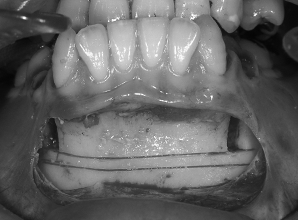

4. 切開します

下のあごの手術を始めます。骨を切って、削って後ろに下げるために必要な範囲を切開します。下くちびるの裏側に3cmくらいの小さな切開をします。薄い粘膜だけを切開します。

切開にはメスや電気メスを使用して、他の組織を傷つけません。切った部分からガーゼを使って優しく手指で伸ばすと、粘膜の下にオトガイ筋、下唇下制筋、オトガイ神経などが透けて見えます。傷つけないように慎重に次の作業に進みます。

5. 剥離します

剥離(はがすこと)は、骨を削るために必要な骨の面が見えるようにおこないます。ガーゼとスプーンのような器具を使って、神経の走行や出口に注意しながら慎重におこないます。骨の膜である骨膜まで剥がすには、まわりにたくさんの筋肉や血管がありますが、傷をつけない様に丁寧に剥がします。

骨膜に到達したら、骨膜はメスを使って切り離します。

骨を切ったり、削除したりする部分だけを露出させます。きれいに骨が露出できれば、骨がきれいに切れて、手術後の出血が少なく、腫れも少なく、治りが早くなります。また、きれいな切開と剥離は、不自然な表情にならないように手術が終わって縫う時に役立ちます。